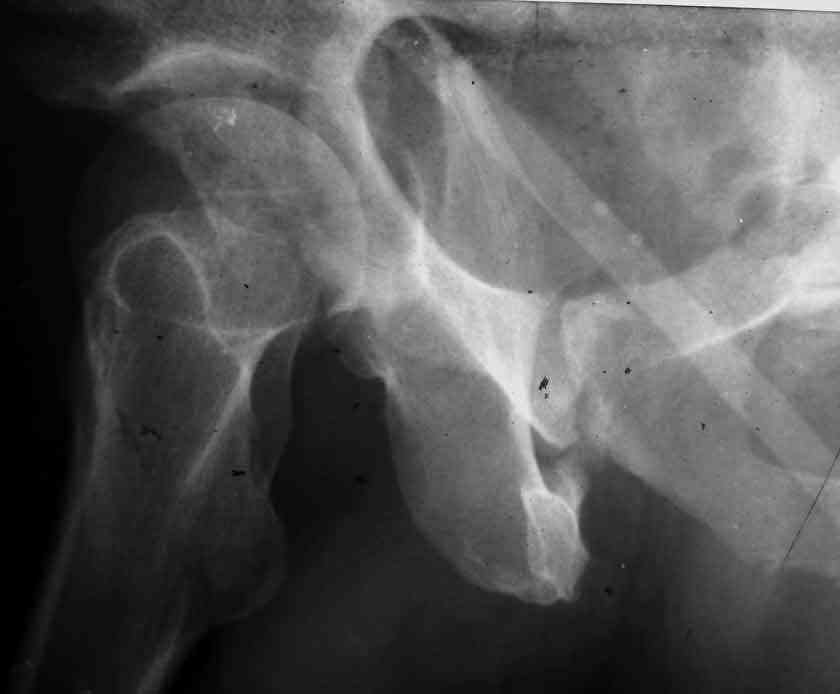

Dear Sir it looks quite difficult classify this fracture because the iliac view is not so clear.

In my opinion it is a column fracture because the obturator foramen is interrupted. There is a fracture of the posterior wall. If we assume the ap view as an iliac view it could be an anterior comun fracture plus posterior wall. It is difficult also to judge the head of the femur.

If you have not a CT scan I think that in order to have a good classification you should obtain a better view of the judet x rays.

From the x rays it appears like a bicolumnar fracture with iliac extension (AO C1).